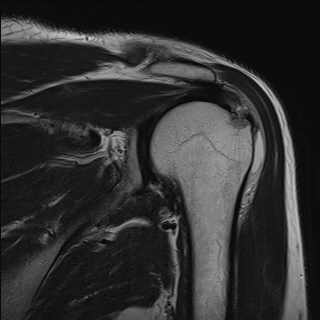

±Ø»ó°Ç ÆÄ¿­, Á¡¾×³¶¿°, °ßºÀÇÏ °ñ±Ø

³»ÃøÀÇ ºÎÁ¾°ú Ç¥Ãþ ¶Ç´Â ÀüÃþ ÆÄ¿­ÀÌ ÀÖÀ¸¸é¼­ Á¡¾×³¶ÀÇ ºÎÁ¾°ú Ãæµ¹°Ë»ç ½Ã Ãæµ¹ ¼Ò°ßÀ» º¸ÀÌ´Â °æ¿ì¿¡

¹æ»ç¼±À̳ª ÀÚ±â°ø¸í°Ë»ç¿¡¼­ º¸ÀÌ´Â °ñ±ØÀÌ ±Ø»ó°Ç ÆÄ¿­ÀÇ ¿øÀÎÀ¸·Î ÃßÁ¤ÇÒ ¼ö ÀÖ´Ù.